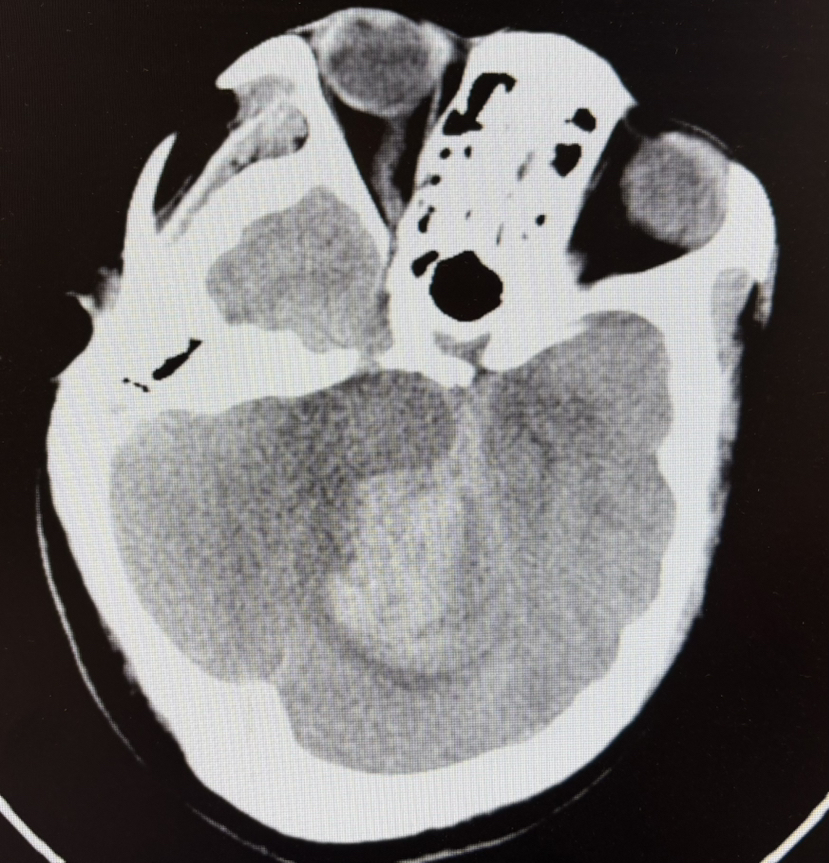

1期术前CT示:小脑出血

1期术后CT

1期术前CTA示:中脑后方AVM

1期术前CTA